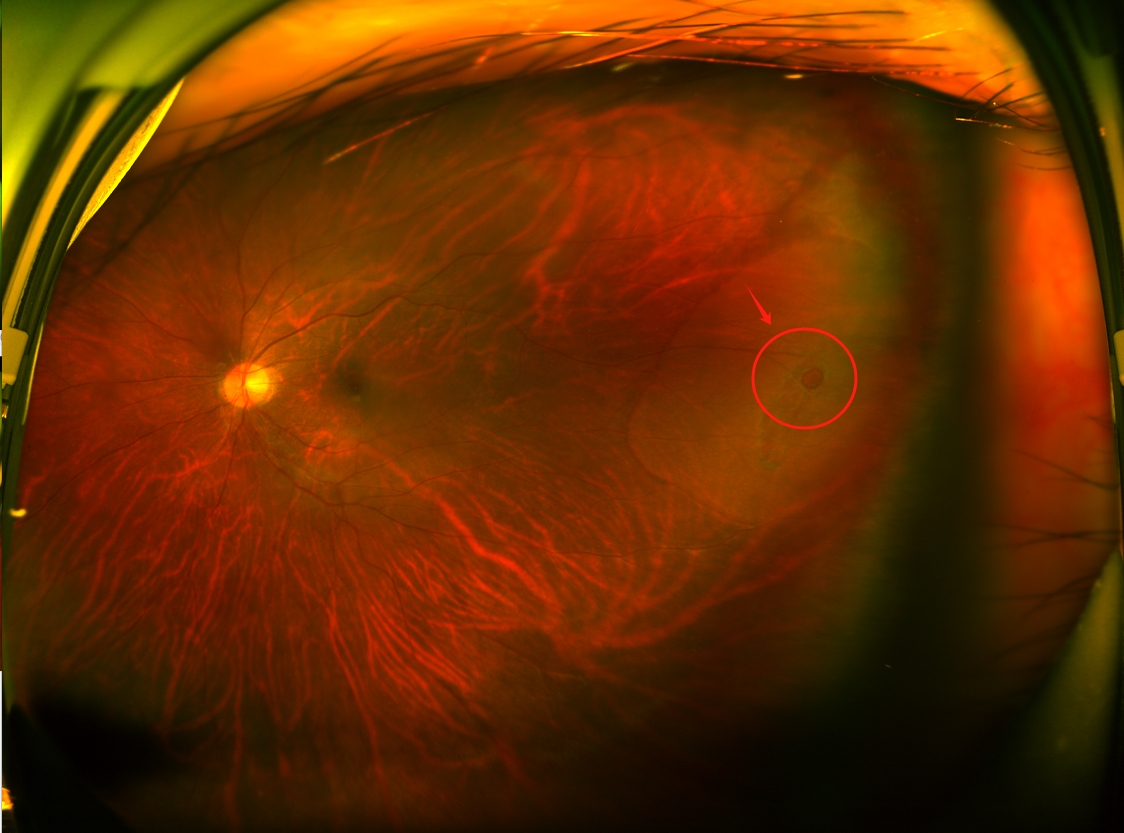

💢视网膜裂孔有多可怕?▶️眼睛突然出现👉飞蚊乱舞+固定黑影+视力骤降▶️严重会导致👉视网膜脱落(24小时极速致盲!)▶️苏伟主任警告:玻璃体牵拉就像"墙皮脱落",拖到晚期手术成功率暴跌3倍!

💉治疗黑科技:⚡激光光凝术→门诊10分钟封印裂孔(像焊死墙壁裂缝)⚡微创玻切术→视网膜脱离急救神器(术后第二天可看清报纸)⚠️苏伟医生私藏Tips:术后千万别揉眼!剧烈运动=自杀式蹦极!